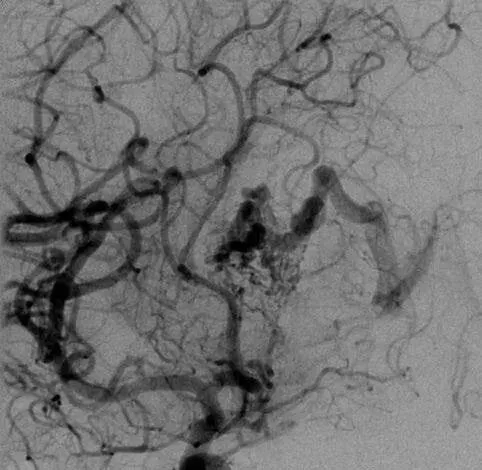

4年前,Emma因突发头痛、呕吐被送医,检查发现是脑室内出血,元凶正是位于透明隔的脑动静脉畸形。Spetzler-Martin分级高达5级(此为最高级别,手术难度和风险极大)。

该AVM由ACA/PcaA分支、ACoA穿支和mPChA供血

右侧ICA造影